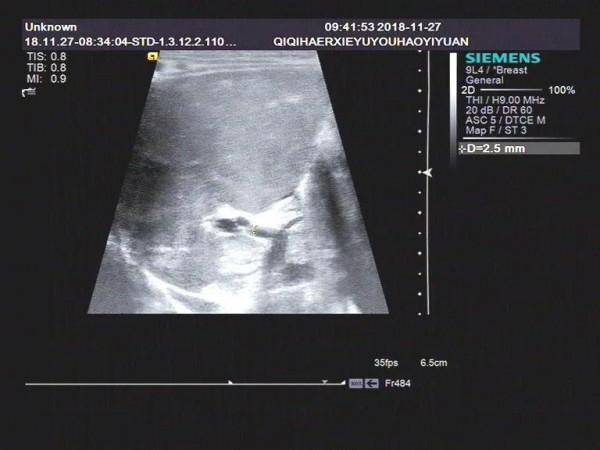

病例2

1)膽囊大小尚正常,但形態僵硬,邊緣不自然。長度可達到2cm左右,內徑大於0.4cm,可有小的憩室樣結構,部分形似臘腸。

2)小膽囊,長度小於1.0~1.5cm,內徑0.2cm,充盈差。

3)膽囊小而且無充盈,僅可見膽囊痕跡。

膽囊的聲像主要表現為:飢餓和餐後狀態下(建議進奶0.5小時,1小時多次觀察),膽囊形態均偏小或有假腔僅呈縫隙狀液性暗區。膽囊切面形態失常、不規則,壁毛糙,僵硬,部分病例可見雙邊回聲,進食後膽囊大小無變化。